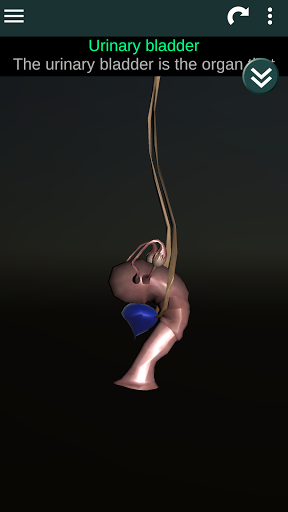

Menampilkan model anatomi 3D dari organ utama tubuh manusia dan penjelasannya masing-masing.

Apa yang ada di aplikasi?

* Mudah diakses dan dinavigasi (zoom, rotasi 3D).

* Deskripsi masing-masing organ.